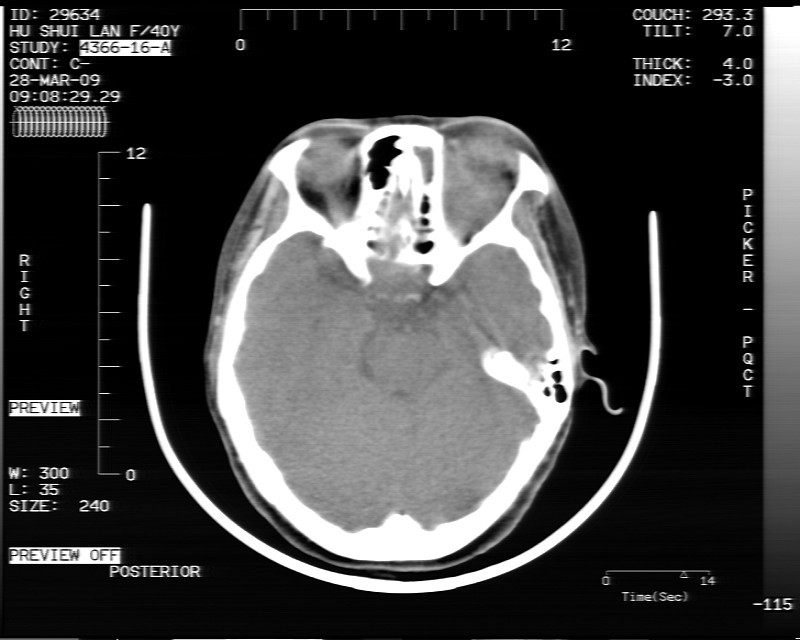

女性,40岁,左眼疼痛,视力模糊,五年曾行左眼脂肪瘤手术。

患者现病史不知持续有多久了,现片示眶内病灶边缘较模糊,眶脂混浊,多考虑炎性假瘤,不除外肿瘤

1)左眼眶内占位性病变,性质待定(不排除炎性假瘤);建议行进一步检查。2)左侧额窦炎。